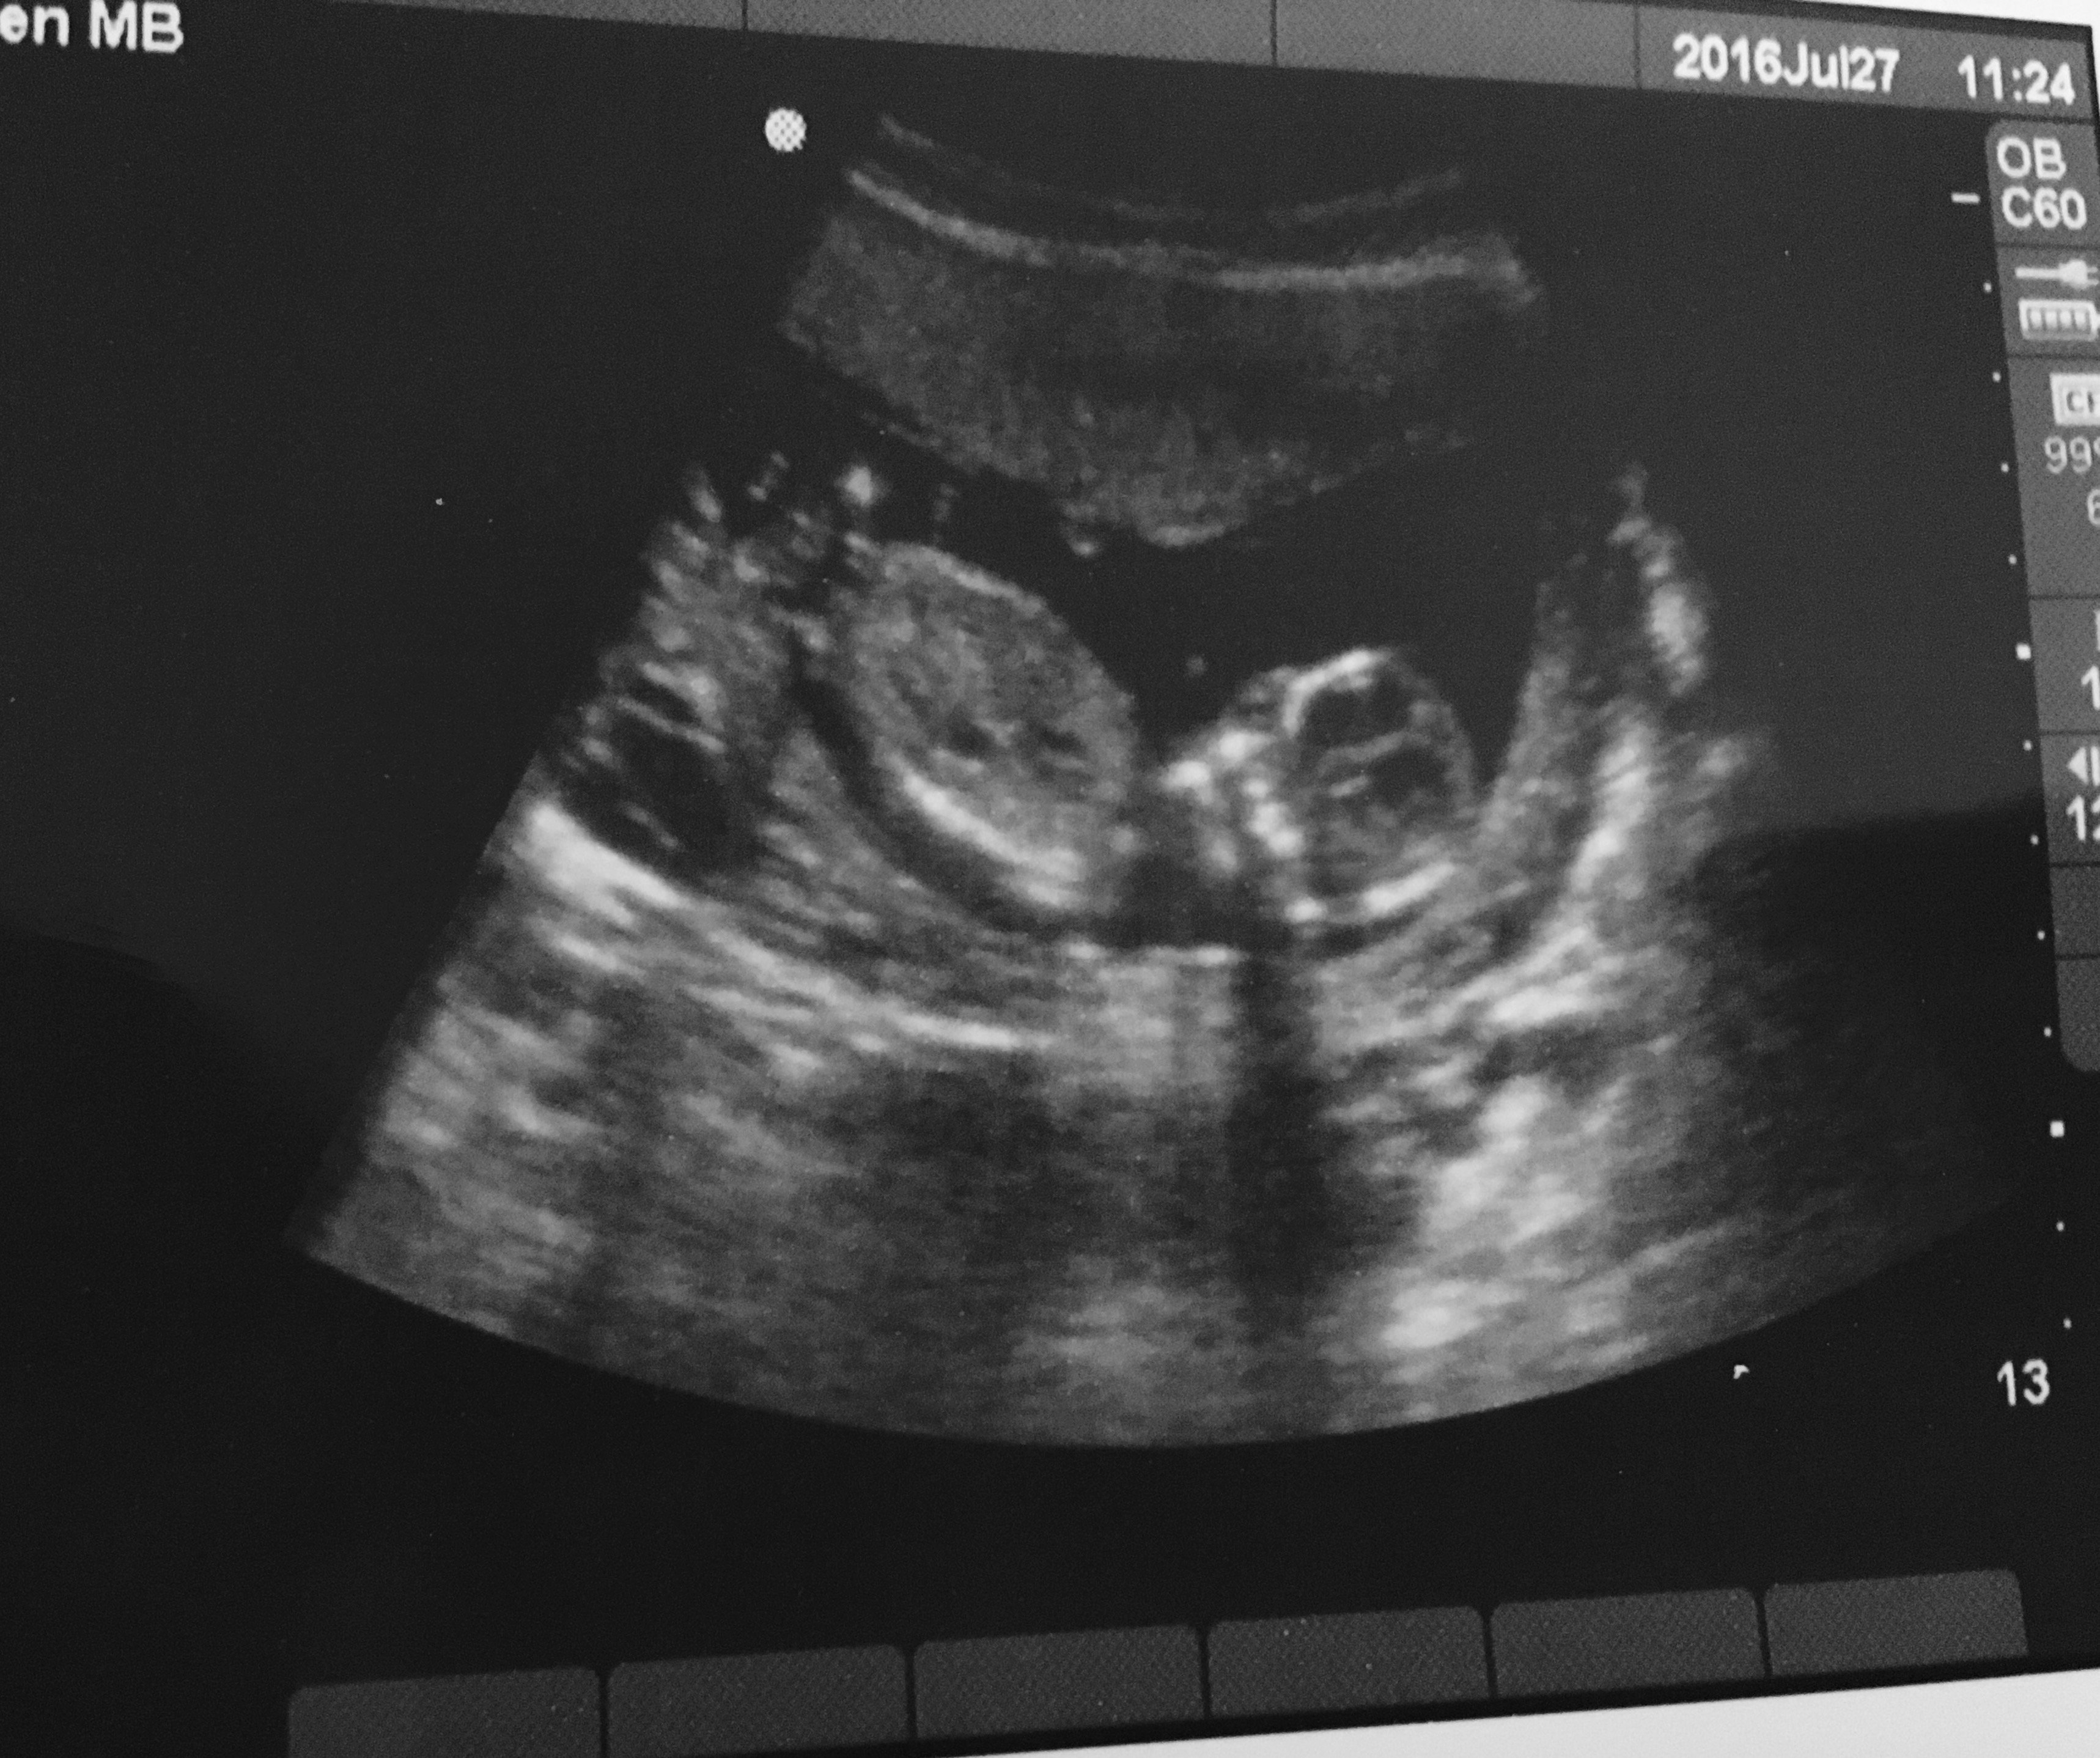

14 week sonogram today. Anyway to tell gender from this? I go for a gender ultrasound in a week and a half but looking for guesses 💗💙

Looks like the baby is facing us? If so can't tell the nub.

Yeah I wasn't sure if there's a nub. Especially since I'm 14 weeks. Just looking for gender guesses in general I guess